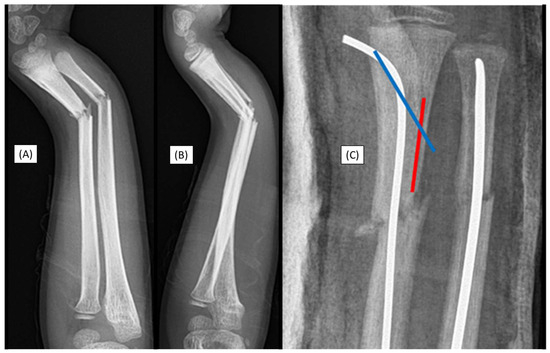

3.1. Case 1: Iatrogenic Cortex Perforation